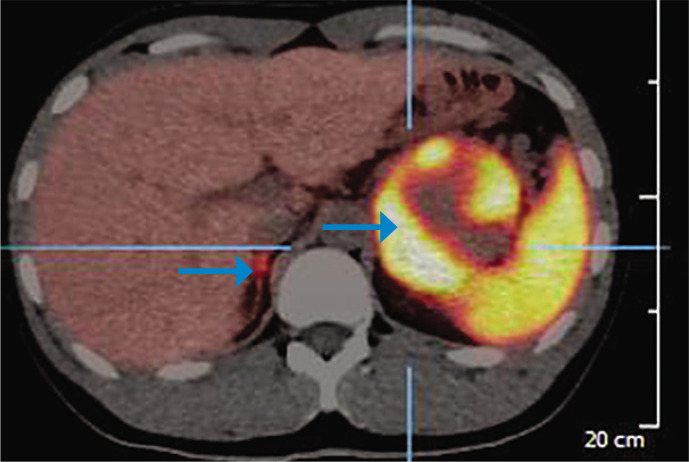

嗜铬细胞瘤和副神经节瘤综合征根据其潜在的遗传改变分为三种特定的疾病群。影响髓细胞瘤病相关因子X (MAX)基因的致病变异易使嗜铬细胞瘤和副神经节瘤综合征发生在更年轻的年龄,其中一半以上患有双侧嗜铬细胞瘤。我们报告一例双侧嗜铬细胞瘤,在MAX基因(c.234_235dup)中发现了一种新的致病变异。这位年轻的男性在表现出严重的高血压和心肌梗塞后被发现有一个巨大的左肾上腺上肿块。他的内分泌检查证实了嗜铬细胞瘤的诊断,尿中去甲肾上腺素、肾上腺素和3-甲氧基酪胺水平升高。肾上腺CT示双侧肾上腺肿物;左侧肾上腺肿块最宽直径约为8cm,右侧肾上腺肿块最宽直径约为2cm。68镓- dotatate功能成像显示左侧肾上腺肿块明显摄取,但右侧不确定,其他地方未见明显摄取提示转移灶。他没有多发性内分泌瘤、神经纤维瘤病或von Hippel Lindau病相关的综合征特征。这些共同的发现提出了是否应该进行单侧或双侧肾上腺切除术的临床困境。因此,致病MAX基因的检测对于指导个性化治疗策略至关重要。在双侧肾上腺切除术后,他的高血压被治愈了。根据国际共识,计划每年进行一次生化筛查和每两年进行一次MRI检查以寻找嗜铬细胞瘤的复发。

Pheochromocytomas and paragangliomas syndrome are grouped into three specific disease clusters based on their underlying genetic alterations. Pathogenic variants affecting the myelocytomatosis-associated factor X (MAX) gene predispose pheochromocytomas and paragangliomas syndrome to occur at younger ages, with more than half having bilateral pheochromocytomas. We report a case of bilateral pheochromocytomas with a novel pathogenic variant identified in the MAX gene (c.234_235dup). This young male was found to have a huge left suprarenal mass after he presented with severe hypertension and myocardial infarction. His endocrine workup confirmed a diagnosis of pheochromocytoma as evidenced by elevated levels of normetanephrine, metanephrine, and 3-methoxytyramine in the urine. CT of the adrenal glands revealed bilateral adrenal masses; the widest diameter for the left adrenal mass was almost 8 cm whereas for the right one was 2 cm. 68Gallium-DOTATATE functional imaging showed significant uptake in the left adrenal mass, but indeterminate on the right, and no significant uptake was seen elsewhere to suggest metastatic lesions. He did not have syndromic features associated with multiple endocrine neoplasia, neurofibromatosis or von Hippel Lindau disease. The collective findings raised the clinical dilemma of whether unilateral or bilateral adrenalectomy should be pursued. The detection of pathogenic MAX gene was therefore crucial in guiding personalized treatment strategy. Following the bilateral adrenalectomy, his hypertension was cured. Annual biochemical screening and 2-yearly MRI imaging to look for recurrence of pheochromocytomas were planned according to international consensus.